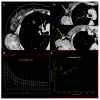

Dual-energy computed tomography (DECT) is one of the most promising technological innovations made in the field of imaging in recent years. Thanks to its ability to provide quantitative and reproducible data, and to improve radiologists' confidence, especially in the less experienced, its applications are increasing in number and variety. In thoracic diseases, DECT is able to provide well-known benefits, although many recent articles have sought to investigate new perspectives. This narrative review aims to provide the reader with an overview of the applications and advantages of DECT in thoracic diseases, focusing on the most recent innovations. The research process was conducted on the databases of Pubmed and Cochrane. The article is organized according to the anatomical district: the review will focus on pleural, lung parenchymal, breast, mediastinal, lymph nodes, vascular and skeletal applications of DECT. In conclusion, considering the new potential applications and the evidence reported in the latest papers, DECT is progressively entering the daily practice of radiologists, and by reading this simple narrative review, every radiologist will know the state of the art of DECT in thoracic diseases.